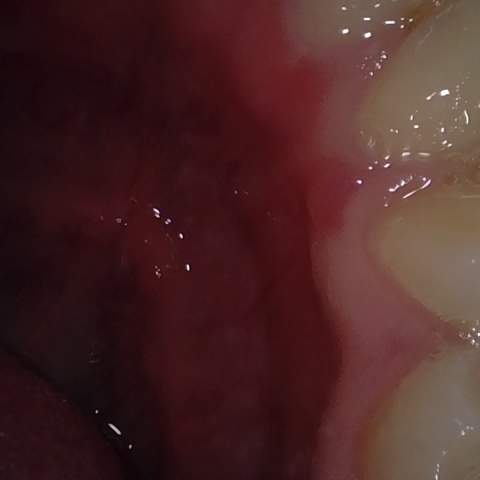

Image 215 / 400

NHD20738

Annotated as "Good"

Original Image Rendering Image